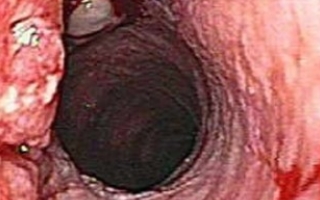

흔한 감기, 위산 역류 그리고 어떤 약물들을 가끔 삼키는 걸 어렵게 만들 수 있다. 시간이 지나도 나아지지 않거나 제산제를 투여해도 소용이 없다면 병원을 찾아야 한다. 삼키는 데 문제가 있다는 것은 식도암의 징후일 수 있다. 생리 주기가 아님에도 불구하고 생기는 출혈은 섬유종이나 피임약이나 기구 등 많은 원인이 있을 수 있다. 폐경기 이후에 출혈이 있다면 정상적인 상황이 아니므로 반드시 진찰을 받아야 한다.